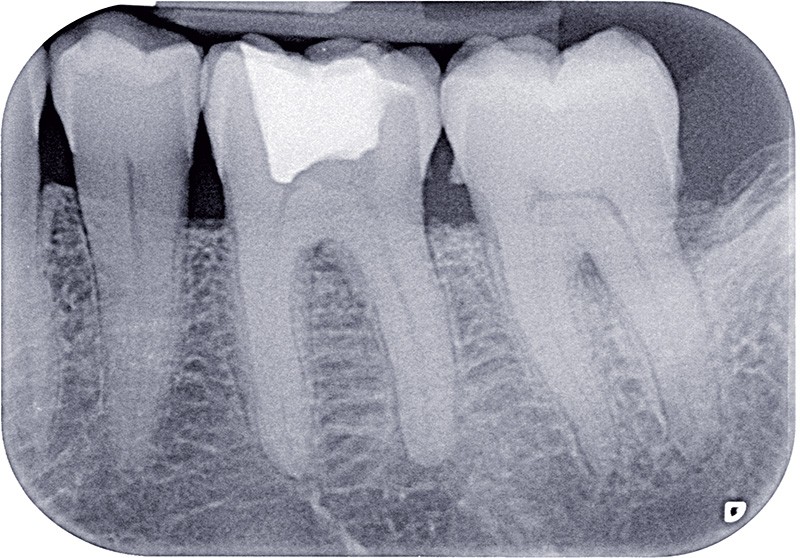

Dans ces situations, le praticien est conduit à dépulper et à restaurer les dents traitées endodontiquement. Les traitements doivent alors s’inscrire dans le concept du continuum endo-restaurateur qui a été défini comme étant « le processus spatio-temporel sans interruption ni rupture qui débute par l’accès à l’endodonte et s’achève avec la mise en place de la restauration prothétique d’usage » (1). Il existe bien une continuité, du traitement endodontique à la restauration fonctionnelle d’usage qui conditionne le pronostic et les résultats du traitement à long terme (fig. 2).